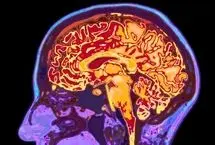

پیری مغز فقط به ژنتیک و سبک زندگی بستگی ندارد؛ یک عامل انسانی شگفتانگیز میتواند این روند را تا ۲۰ درصد کندتر کند.